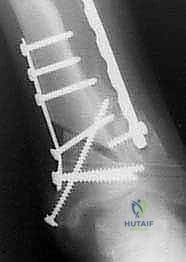

5. التثبيت الداخلي القوي (Internal Fixation)

بعد الوصول للزاوية المثالية التي تم حسابها مسبقاً، يتم تثبيت العظم بإحكام شديد باستخدام شرائح معدنية متطورة (Locking Plates) ومسامير من التيتانيوم. هذا التثبيت القوي هو ما يسمح للمريض ببدء الحركة والتأهيل مبكراً.